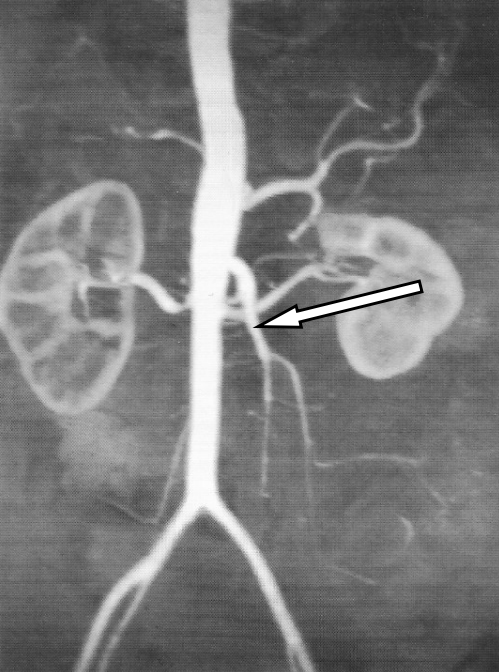

Którą tętnicę zaznaczono strzałką na obrazie MR?

A. Krezkową górną.

B. Śledzionową.

C. Krezkową dolną.

D. Nerkową lewą.